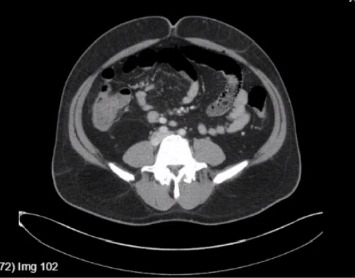

背景:伤寒是一种由伤寒沙门菌和副伤寒沙门菌引起的多系统疾病,可通过受污染的水和食物经粪便经口传播。在美国,这是一种罕见的诊断,大多数病例报告发生在返回的旅行者身上。肝炎和胆汁淤积是沙门氏菌感染的罕见后遗症。然而,急性肝衰竭(ALF)是非常罕见的。我们报告一例伤寒在返回旅行者到美国进展到ALF。病例介绍:一名48岁男性,表现为高热、腹痛、呕吐、胆汁性便、尿色深、皮肤和巩膜变黄,持续一周。他对甲型和乙型肝炎有免疫力,近期用药也没有变化。他没有饮酒史。就诊时,患者心动过速,但血流灌注良好,伴有弥漫性腹部压痛。实验室结果显示白细胞增多,肌酐升高,肝酶升高的混合肝细胞和胆汁淤积模式,氨水平升高,溶血参数阴性。病毒性、自身免疫性和代谢性肝炎均为阴性。腹部超声显示胆道系统正常,腹部CT显示多发肝囊肿,肠系膜及肝门淋巴结病变,回肠末端轻度增厚。开始静脉注射头孢曲松和甲硝唑。血液培养培养出伤寒沙门氏菌。患者临床病情恶化,出现精神状态改变、呼吸窘迫,终末期肝病(MELD)评分呈上升趋势,并被升级至重症监护病房。开始静脉滴注美罗培南,临床恢复,重复血培养阴性。患者完成2周美罗培南治疗后出院。结论:伤寒可引起危及生命的肝功能衰竭,但罕见。临床医生应该意识到这一点,因为它的进展迅速,临床病程危及生命,而且耐多药和广泛耐药伤寒的增加导致开始使用正确抗生素的延误。

Background: Typhoid fever is a multisystemic illness caused by Salmonella typhi and Salmonella paratyphi, transmitted fecal orally through contaminated water and food. It is a rare diagnosis in the US, with most cases reported in returning travelers. Hepatitis and cholestasis are rare sequelae of salmonella infection. However, acute liver failure (ALF) is exceptionally uncommon. We report a case of typhoid fever in a returning traveler to the US progressing to ALF. Case Presentation: A 48-year-old man presented with high-grade fever, abdominal pain, vomiting, acholic stools, dark urine, and yellowish discoloration of skin and sclera for one week. He was immune to hepatitis A and B, with no recent change in medications. He had no history of alcohol consumption. On presentation, the patient was tachycardic but well perfused with diffuse abdominal tenderness. Laboratory results showed leukocytosis, elevated creatinine, mixed hepatocellular and cholestatic pattern of raised liver enzymes, elevated ammonia levels, and negative hemolytic parameters. Viral, autoimmune, and metabolic causes of hepatitis were negative. Ultrasound of the abdomen revealed a normal biliary system and a computerized tomography (CT) scan of the abdomen showed multiple liver cysts, mesenteric and porta-hepatis lymphadenopathy, and mild thickening of the terminal ileum. Intravenous (IV) ceftriaxone and metronidazole were initiated. Blood cultures grew S. typhi. The patient clinically deteriorated and developed altered mental status, respiratory distress, and an up-trending Model for End-Stage Liver Disease (MELD) score and was upgraded to the intensive care unit. IV meropenem was initiated, resulting in clinical recovery and negative repeat blood cultures. The patient completed 2 weeks of meropenem and was discharged. Conclusion: Typhoid fever can cause life-threatening liver failure which is rare. Clinicians should be aware of this due to the rapid progression and life-threatening clinical course, as well as the rise of multidrug-resistant and extensively drug-resistant typhoid causing delays in starting the right antibiotic.